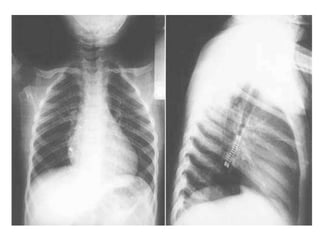

Left X-ray shows air trapping ; right X-ray (different patient) shows atelectasis

Chest X-ray forAspirated Foreign Bodies ƒ Foreign object radiopaque in 6 to 20 % ƒ CXR normal in 18 to 33 % ƒ CXR findings: –obstructive emphysema –atelectasis –pneumonia ƒ Expiratory film enhances CXR yield

Left X-ray showsair trapping ; right X-ray (different patient) shows atelectasis